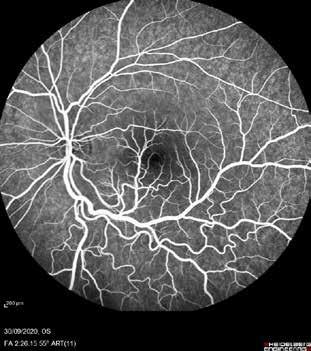

Type 3 MNV refers to the growth of vessels from the retinal circulation toward the outer retina. It is believed that vascular proliferation begins in the deep retinal capillary plexus, with the growth vector extending toward the outer retina. On FA and ICGA, Type 3 MNV appears as a hyperfluorescent intraretinal vascular complex with leakage in the late phases of the examination. Late-phase leakage ion ICGA is a unique feature of MNV lesions. Since these lesions originate from the retinal circulation, they never arise within the foveal avascular zone. Instead, they develop near its edge or at a variable distance from it, typically from the terminal portions of third-order arterioles and venules.5 (Figure 3)

Figure 3. Two examples of Type 3 macular neovascularization. In the first case, Indocyanine green angiography (B) and fluorescein angiography revealing the Type 3 macular neovascularization (arrowhead). Optical coherence tomography (C) showing the detachment of retinal pigment epithelium with the hyperreflective material related to the neovascularization. In the second case, optical coherence tomography (E) showing the intraretinal hyperreflective material related to the neovascularization with intraretinal fluid. Fundus autofluorescence (F) showing abnormalities of retinal pigment epithelium. Optical coherence tomography angiography (G) showing the neovascular lesion.